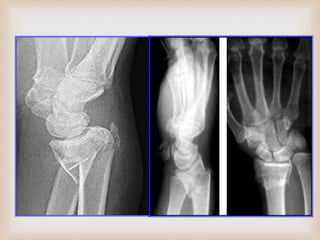

 La evaluación radiográfica incluye proyecciones antero-posterior

(AP), lateral (L) y oblicua que deben mostrar la extensión y

dirección del desplazamiento inicial.

 Tras la reducción cerrada deberán repetirse las radiografías para

identificar la deformidad residual y el grado de conminución.